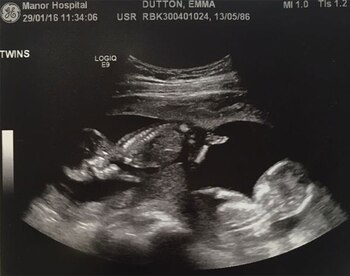

Emma Dutton, en pareja con Mark Prince, tiene 30 años y durante un largo tiempo intentó, sin éxito, ser madre. Esta familia de Walsall, West Midlands, recurrió a un tratamiento de fertilización hasta que la genial noticia llegó a sus vidas: serían padres ¡de gemelos!

Impactados por la espectacular novedad, comenzaron a planificar sus días de a cuatro. Sin embargo, su felicidad plena no duró tanto como hubieran pretendido. En una sala del centro médico en el que se atendían, uno de los obstetras les informó algo que no querían escuchar: los embriones estaban sufriendo una rara enfermedad que ponía en riesgo sus vidas.

Dos semanas después, cuando se cumplían cinco meses, los volvieron a reunir. Esta vez para decirles que uno de los gemelos había muerto en su vientre. Quedaron devastados, no podía ser de otra forma. ¿Debían regresar en poco tiempo para que el cuadro empeorase? Los pensamientos atormentaban a Emma y Mark, pero era ella quien llevaba la peor parte.

Los médicos fueron sinceros. Para evitar un desenlace semejante en el otro pequeño, debía llevar a su bebé muerto en su interior durante el resto del embarazo, o al menos hasta el momento en que Oliver —así llamaron a su bebé— estuviera listo para nacer. Decidieron correr el riesgo. La valentía y voluntad de Emma eran absolutas y supo que podría lograrlo.

A las 35 semanas y cuatro días, Oliver nació con excelente salud. Además, los médicos también sacaron a Elijah, sin vida. Emma dice que es feliz por haber permitido que ambos salieran de su vientre al mismo tiempo, a pesar de las durísimas circunstancias que rodearon su embarazo.

Los hermanos sufrieron el síndrome de transfusión de gemelo a gemelo (TTTS, por sus siglas en inglés), que es una complicación severa que afecta a entre el 10 y el 15 por ciento de los embarazos múltiples que comparten placenta. "Ahora pienso que quiero hacer algo para y reunir dinero para investigación para que otras familias no tengan que pasar por lo mismo que yo", contó la joven madre.